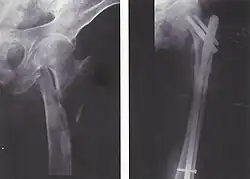

| Fratura da diáfise do fêmur com deslocamento e fragmentos. | |

Para fraturas da diáfise, a redução e haste intramedular são recomendados atualmente. O osso é realinhado, e em seguida uma haste de metal é fixada atravessando a medula óssea. A haste é estabilizada com pregos em cada extremidade. Este método oferece menos exposição, 98% de consolidação, menores taxas de infecção (1%-2%) e menos cicatrizes.[13]